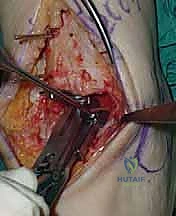

5. القطع العظمي الظنبوبي (Tibial Bone Cut)

باستخدام منشار جراحي دقيق التذبذب، يتم إزالة شريحة رقيقة جداً (بضعة مليمترات) من السطح السفلي التالف لعظمة الظنبوب. يتم القطع بحذر شديد لتجنب إصابة الأوتار الخلفية أو الأوعية الدموية.

6. القطع العظمي الكاحلي (Talar Bone Cut)

بشكل مشابه، يتم توجيه دليل القطع نحو عظمة الكاحل (Talus) وإزالة السطح الغضروفي التالف وت